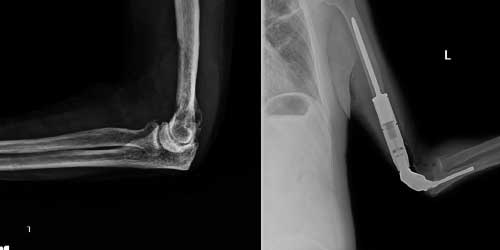

Her ameliyatın olduğu gibi kemik ve yumuşak doku tümör ameliyatlarının da riskleri vardır. Bu riskleri genel ve yapılan ameliyata özgü olmak üzere kabaca iki başlık halinde gruplandırabiliriz. Öncelikle anestezi ile ilgili risklerin anestezi uzmanı tarafından (...)

Ameliyat sonrası takip ve kontrol hastanın ameliyat masasında uyanması ile başlar. Özellikle damar ve veya siniri ilgilendiren ameliyatlarda hasta ameliyat masasından alınmadan ekstremitenin dolaşımı ve ilgili sinirin fonksiyonu kontrol edilir.